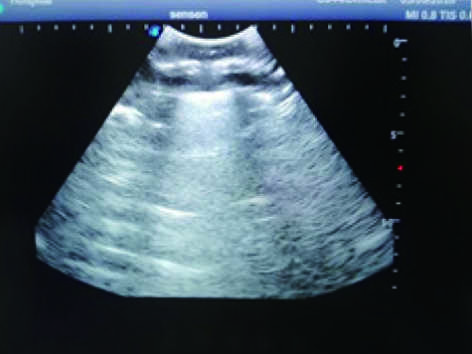

2) Real clinical ultrasound images with clear muscles, connective tissues, lungs and pleural structures